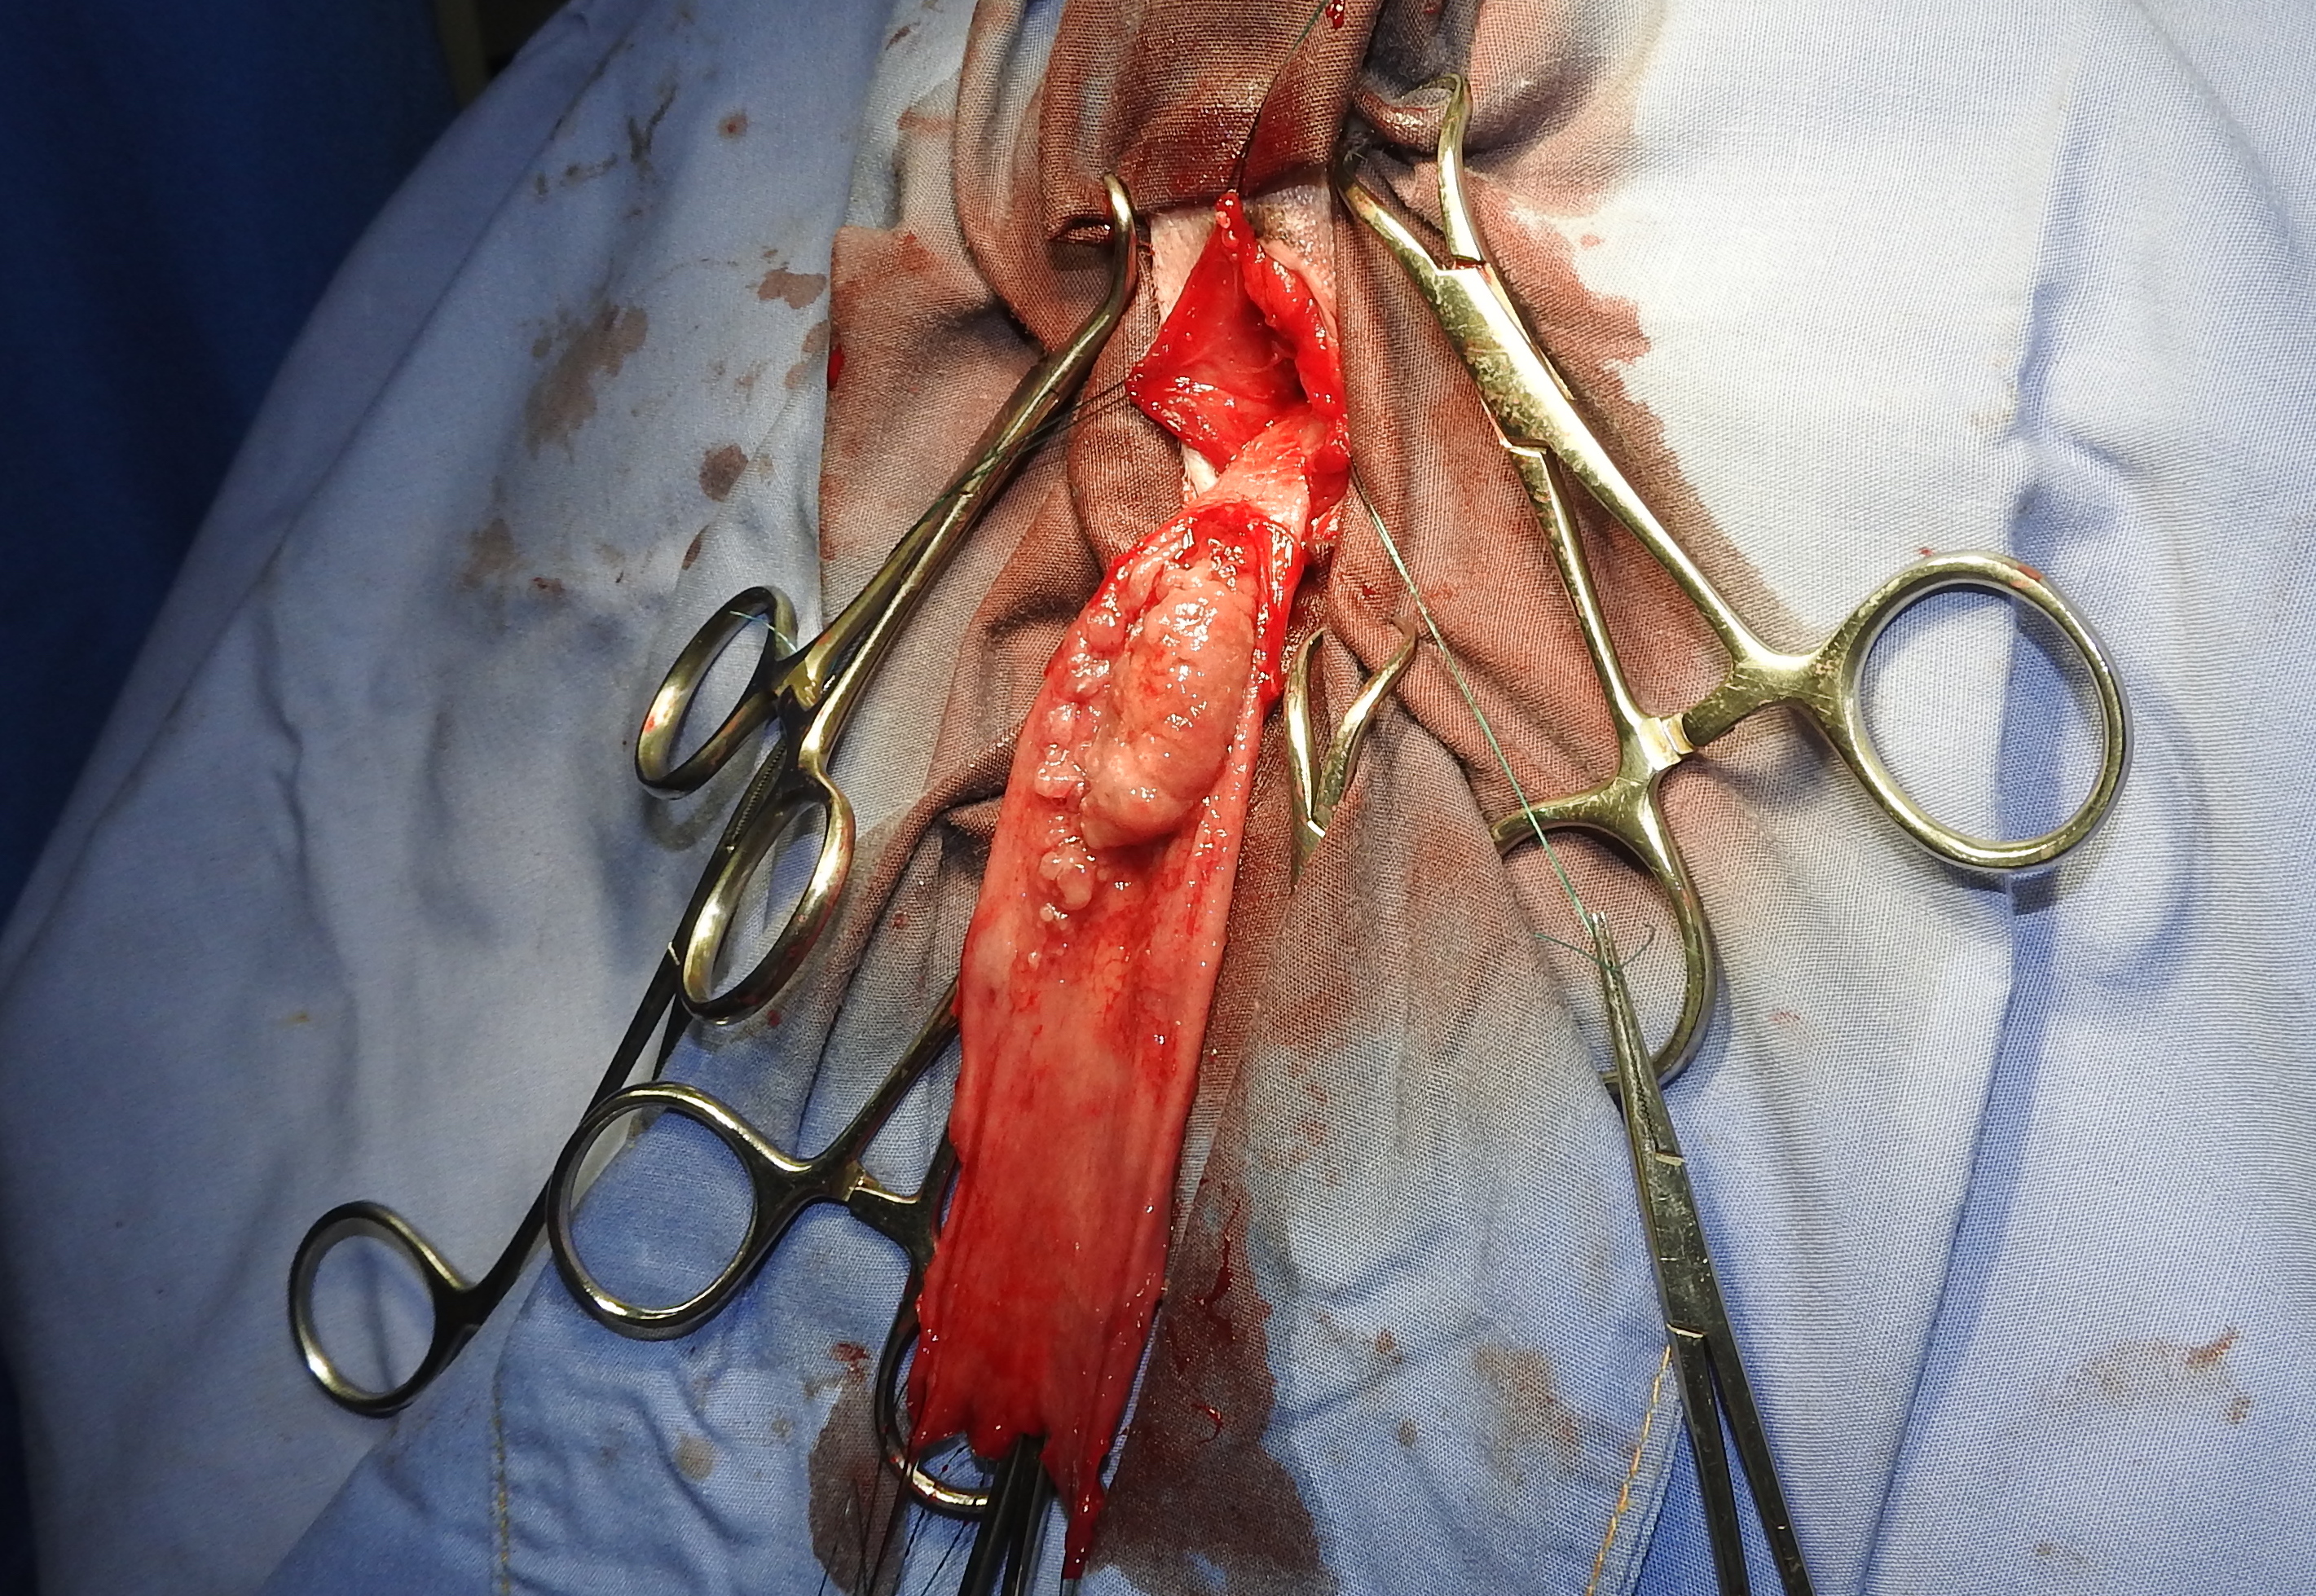

画像・写真|『週刊プレイボーイ』38号表紙(c)yorokobi/週刊プレイボーイ 2枚目 / 南里美希、シースルーまといセクシーグラビア 大人の色気直腸プルスルー法を用いて直腸切除術を行いました。 肛門から直腸を引き抜いてきて切除する術式です。 ①まずは、肛門から直腸粘膜を引きずり出します。 病変の広がりを把握するため、肛門から15cm程度離れた病変のない部位を切開します。 ②切開し 元気可愛いプルスルーブレイドアレンジ♪6 サイド&バックスタイル 画像女の子のママさん必見! 元気可愛いプルスルーブレイドアレンジ♪7 アクティブ可愛い髪型でしたよね♪ 手が込んでいる分、とっても豪華ですね! 子供も喜ぶこと

![]() 犬の大腸癌の手術法 新千歳動物病院のブログ | ![]() 犬の大腸癌の手術法 新千歳動物病院のブログ | ![]() 犬の大腸癌の手術法 新千歳動物病院のブログ |

犬の大腸癌の手術法 新千歳動物病院のブログ | 犬の大腸癌の手術法 新千歳動物病院のブログ | ![]() 犬の大腸癌の手術法 新千歳動物病院のブログ |

犬の大腸癌の手術法 新千歳動物病院のブログ | ![]() 犬の大腸癌の手術法 新千歳動物病院のブログ | ![]() 犬の大腸癌の手術法 新千歳動物病院のブログ |